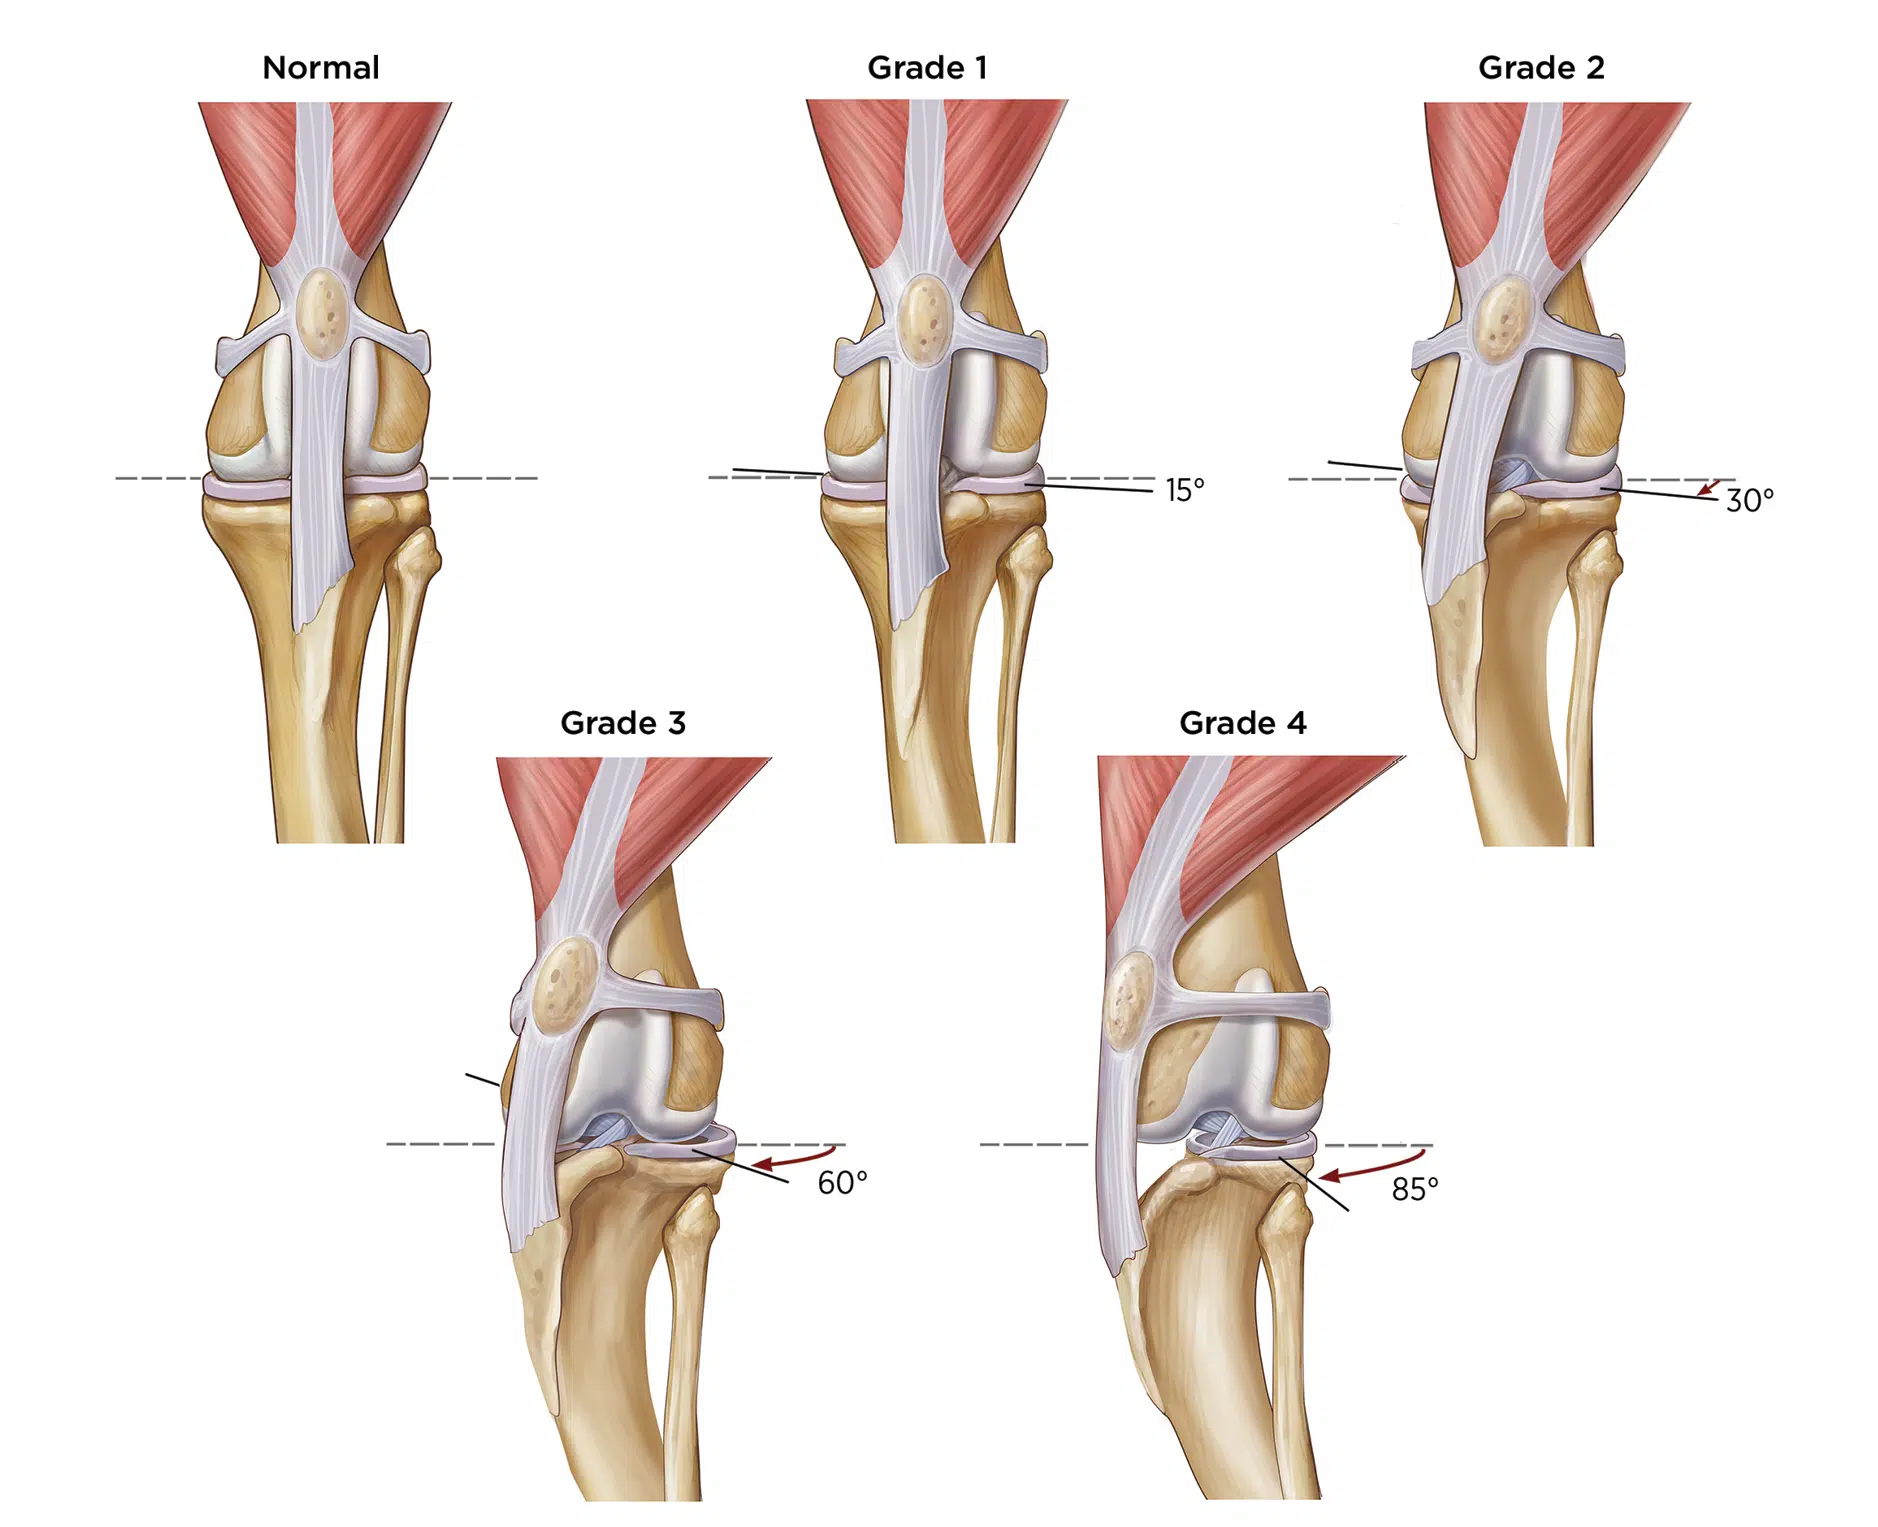

Patellar luxation can be classified according to the level of severity:

- Grade I — Clinical signs are mild and infrequent, and the patella can be manually luxated but easily returns to the trochlear groove.

- Grade II — The patella luxates during flexion of the joint and is repositioned during extension, causing animals to have a resolvable skipping lameness.

- Grade III — the dislocated patella is more frequently out of, instead of in, the trochlear groove, and lameness is consistent. Bone deformities are evident in these animals.

- Grade IV — Lameness and limb deformations are most severe.

- In patients with higher-grade luxations (grades III and IV), soft tissue alterations can be more severe and hind limb conformational changes may be present, resulting from displacement of the quadriceps/patellar tendon mechanism over time.

- For patients with higher-grade III and IV medial PL, the changes can result in outward bowing of the stifles (genu varum) and a bowlegged conformation.

- For patients with higher-grade III and IV lateral PLs, inward bowing of the stifles (genu valgum) may be apparent with a knock-kneed conformation.

- Patients with the most severe PL can lose the ability to extend the stifle due to severe malalignment of the extensor mechanism and development of irreversible soft tissue changes around the stifle joint. Thus, early intervention is key.